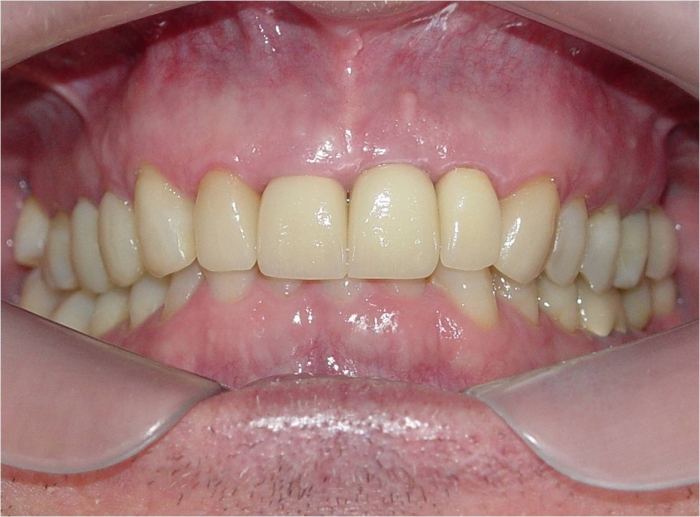

Sorriso final